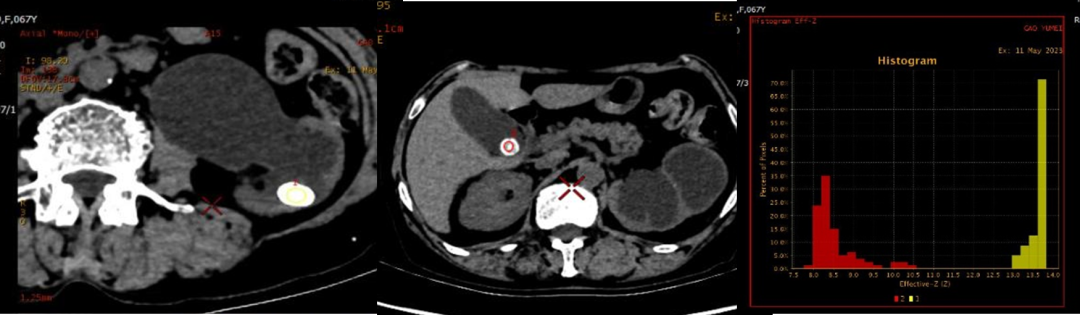

3.有效原子序數(shù)通過(guò)計(jì)算有效原子序數(shù),可進(jìn)行物質(zhì)的檢測(cè)、鑒別及分離,臨床用于結(jié)石成分、痛風(fēng)成分分析等。